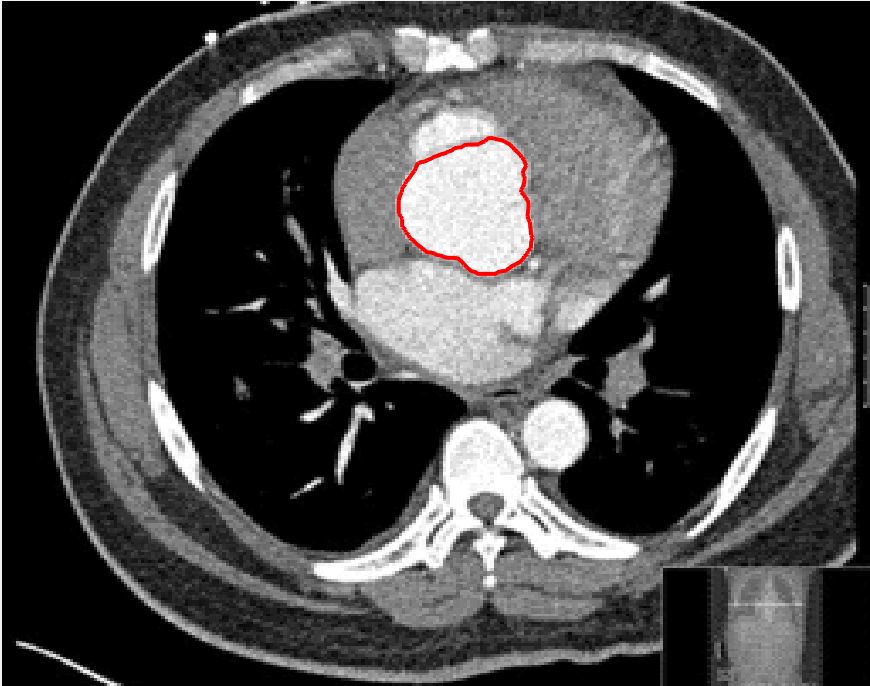

In this test we give the segmentation results for models M1 – M7 for the two challenging test images shown in Figure 9. The marker and anti-marker sets used in the experiments are also shown in this figure. After extensive parameter tuning, the best final segmentation results for each of the models are shown in Figures 10 and 11. For M1 – M4 we obtain incorrect segmentations in both cases. In particular, the results of M2 and M4 are interesting as the former gives poor results for both images, and the latter gives a reasonable result for Test Image 1 and a poor result for Test Image 2. In the case of M2, the regularisation term includes the edge detector and the distance penalty term (see (4)). It is precisely this which permits the poor result in Figures 10(b) and 11(b) as the edge detector is zero along the contour and the fitting terms are satisfied there (both intensity and area constraints) – the distance term is not large enough to counteract the effect of these. In the case of M4, the distance term and edge detector are separated from the regulariser and are used to weight the Chan-Vese fitting terms (see (9)). The poor segmentation in Figure 11(b) is due to the Chan-Vese terms encouraging segmentation of bright objects (in this case), weighting ω𝜔\omega enforces these terms at all edges in the image and near \mathcal{M}. In experiments, we find that M4 performs well when the object to segment is of approximately the highest or lowest intensity in the image, however when this is not the case, results tend to be poor. We see that, in both cases, models M5 and M6 give much improved results to M2 and M4 (obtained by incorporating the geodesic distance penalty into each). The proposed Geodesic Model M7 gives an accurate segmentation in both cases. It remains to compare M5, M6 and M7. We see that M5 is a non-convex model (and cannot be made convex [39]), therefore results are initialisation dependent. It also requires one more parameter than M6 and M7, and an accurate set \mathcal{M} to give a reasonable area constraint in (4). These limitations lead us to conclude M6 and M7 are better choices than M5. In the case of M6, it has the same number of parameters as M7 and gives good results. M6 can be viewed as the model M7 with weighted intensity fitting terms (compare (18) and (30)). Experimentally, we find that the same quality of segmentation result can be achieved with both models generally, however M6 is more parameter sensitive than M7. This can be seen in the parameter map in Figure 12 with M7 giving an accurate result for a wider range of parameters than M6. To show the improvement of M7 over previous models, we also give an image in Figure 13 which can be accurately segmented with M7 but the correct result is never achieved with M6 (or M3). Therefore we find that M7 outperforms all other models tested M1 – M6.

(g) M7 λ=10,θ=1formulae-sequence𝜆10𝜃1\lambda=10,\theta=1.

Figure 10: Visual comparison of M1 – M7 results for Test Image 1. M1 segmented part of the object, M2 – M4 failed to segment the object, M5 gave a reasonable result (though not accurate) and, M6 and M7 correctly segmented the object.